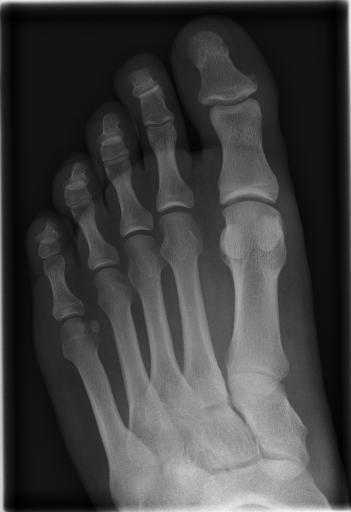

More information on the IRMA database and code can be found in [21, 23, 22]. IRMA dataset offers 12,677 images for training and 1,733 images for testing. Figure 3 shows some sample images from the dataset long with their IRMA code in the format TTTT-DDD-AAA-BBB.